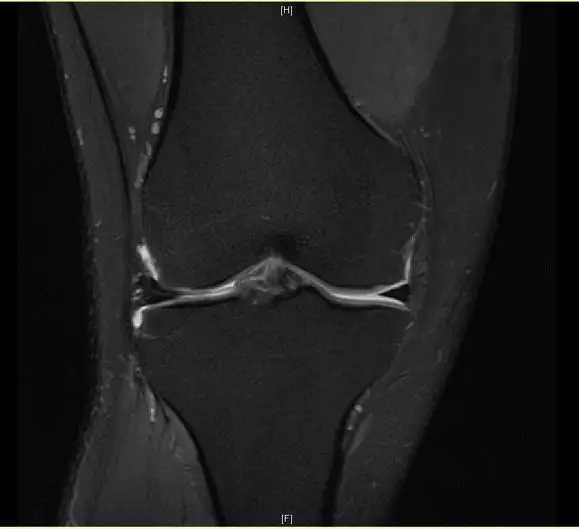

前交叉韧带断裂,外侧半月板后角撕裂

从此片我们可以看到前交叉韧带的上止点高信号,前交叉韧带角度增加,后交叉韧带的夹角增大,从这个层面可以看到外侧半月板边缘不清楚不完整质地不均一,混杂有高信号的改变,并且内部有一些裂隙,从这个层面我们可以看到前交叉韧带的下止点相对比较完整,而这个层面上止点信号异常,韧带松弛并且有大量的渗出病变,缺乏张力。这个层面也可以看到髁间窝这个部位凸起,看不到应有的上止点信号。所以这个病例我们需要考虑前交叉韧带断裂,外侧半月板后角撕裂。